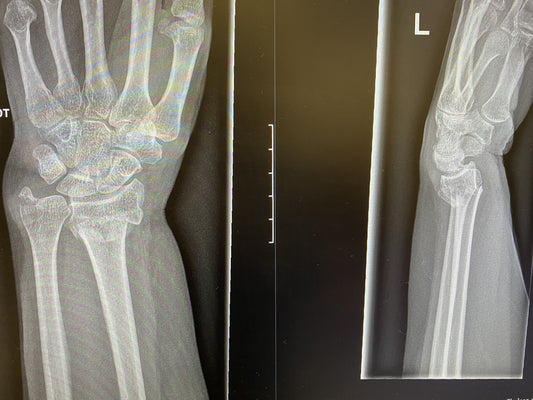

Does a broken wrist need an operation?

Generally when people talk about a broken wrist they mean the end of the radius bone closest to the hand. This is one of the most commonly broken bones in...